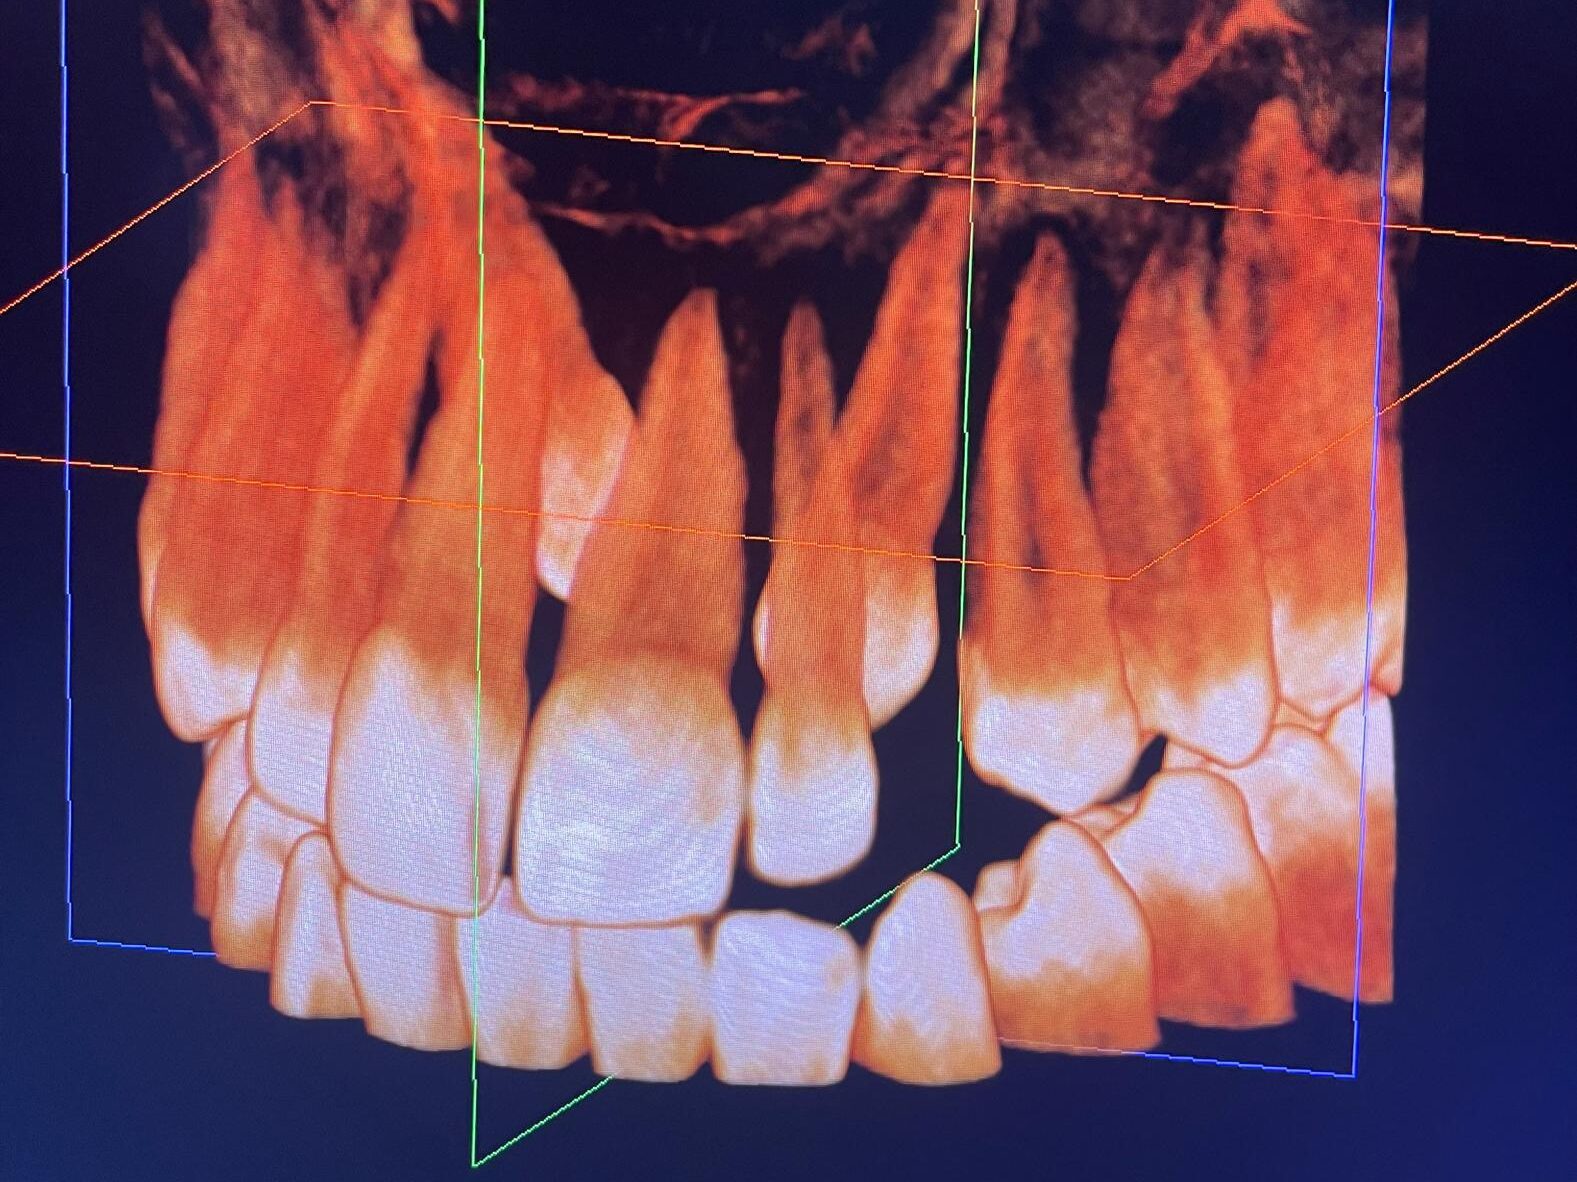

Tomografia komputerowa

Tomografia komputerowa 3D to najbardziej zaawansowana metoda diagnostyczna dostępna w stomatologii. Umożliwia trójwymiarową ocenę kości, zębów, kanałów nerwowych oraz innych struktur anatomicznych twarzoczaszki. Badanie jest szczególnie przydatne przy planowaniu wszczepienia implantów, skomplikowanych zabiegów chirurgicznych, ocenie urazów czy zmian patologicznych. W Poddent w Wieluniu dysponujemy nowoczesnym urządzeniem do tomografii komputerowej, które pozwala uzyskać niezwykle precyzyjne obrazy przy zachowaniu minimalnej dawki promieniowania, co czyni badanie bezpiecznym dla pacjenta. Tomografia komputerowa w naszej klinice to inwestycja w bezpieczeństwo, dokładność diagnostyki i długoterminową skuteczność leczenia.